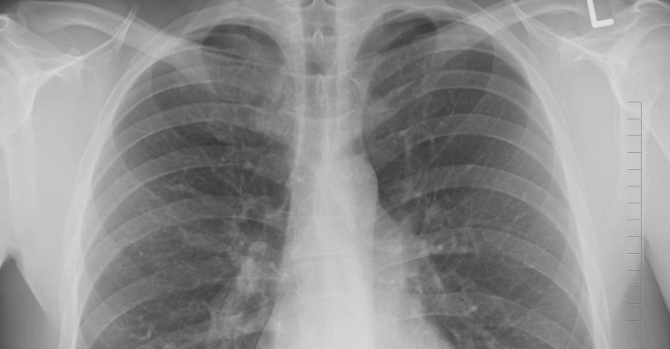

При этом этот вид онкологии признан одним из самых распространенных и опасных, поэтому важно выявить его на начальных этапах. Врачи рассказали, как по кашлю определить рак легких. Как пишет издание «Актуальные новости», ключевым симптомом можно считать затяжной кашель. Насторожить должен кашель, который не проходит более трех недель.

Кроме того, симптомами рака легких можно считать повторяющиеся инфекции грудного отдела, хрипы невыясненной этиологии, боли в груди и плечах, а также осипший голос на протяжении долгого времени. На развитие рака могут указывать необъяснимая потеря веса и постоянное чувство усталости. Медики напоминают, что эти симптомы могут свидетельствовать и о других заболеваниях.